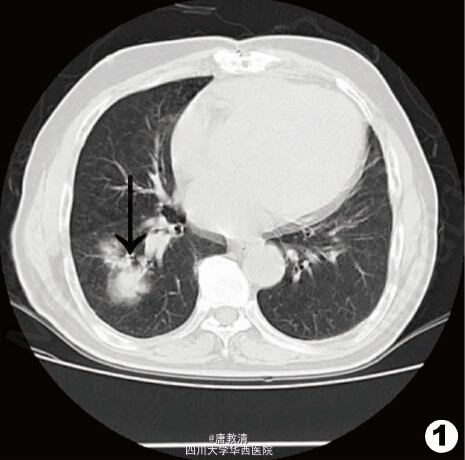

体查:一般状态尚可,右颈部可触及一0.2cm×0.3cm大小淋巴结,质软、活动好、无压痛。心、肺、腹部查体未见异常。 辅助检查:血、尿、便常规及肝肾功能检查未见异常。胸部CT示右肺下叶见4.8cm×3.7cm×4.2cm占位性病变。

结合临床表现、肺部CT与病检结果分析考虑肺癌皮肤转移。 转入肿瘤科进一步治疗。